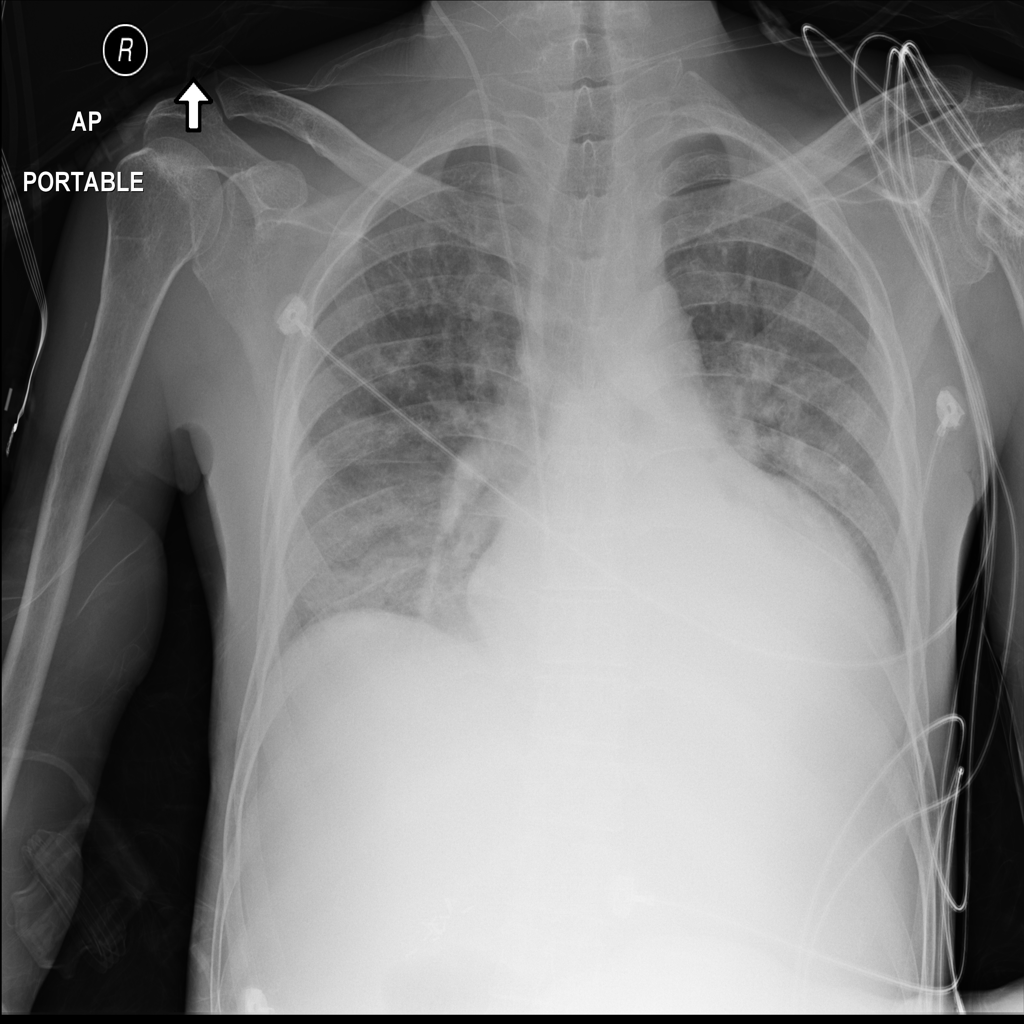

PAT-24D9 · IMG-006Edema

PAT-24D9 · IMG-006

AP